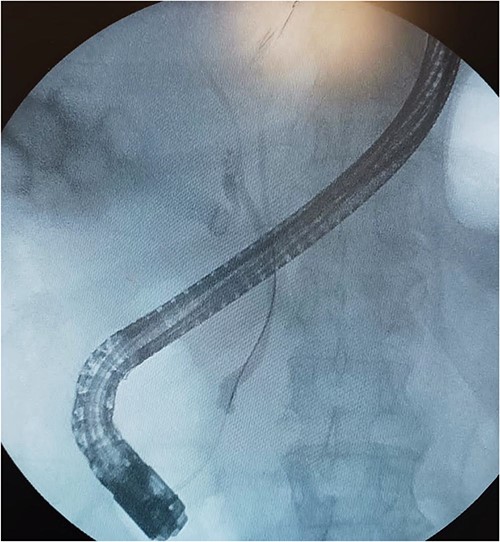

A 61-year-old Mexican man presented to the emergency room with an epigastric pain; he was admitted due to acute pancreatitis of biliary origin and intermediate risk of choledocholithiasis. We performed a magnetic resonance reported, right posterior hepatic duct absence of signal, choledochal with presence of heterogeneous content with absence of signal in intrapancreatic portion of a choledochal duct (Fig. 1). On the endoscopic retrograde cholangiopancreatography (ERCP), a cystic drain of the RHD was found (Fig. 2). Patient presented slow clinical evolution with increased systemic inflammatory response syndrome for which a contrasted computer tomography was performed with findings of pancreatitis with Balthazar C score. Subsequently, an adequate evolution was presented, and the acute picture of pancreatitis is resolved, hospital discharge was performed to an elective laparoscopic cholecystectomy of interval.

Magnetic resonance cholangiopancreatography (MRCP) axial imagen. A: T2W- TSE; B, T2W- SPIR. A and B findings right posterior hepatic duct absence of signal, choledochal with presence of heterogeneous content with absence of signal in intrapancreatic portion (arrows).